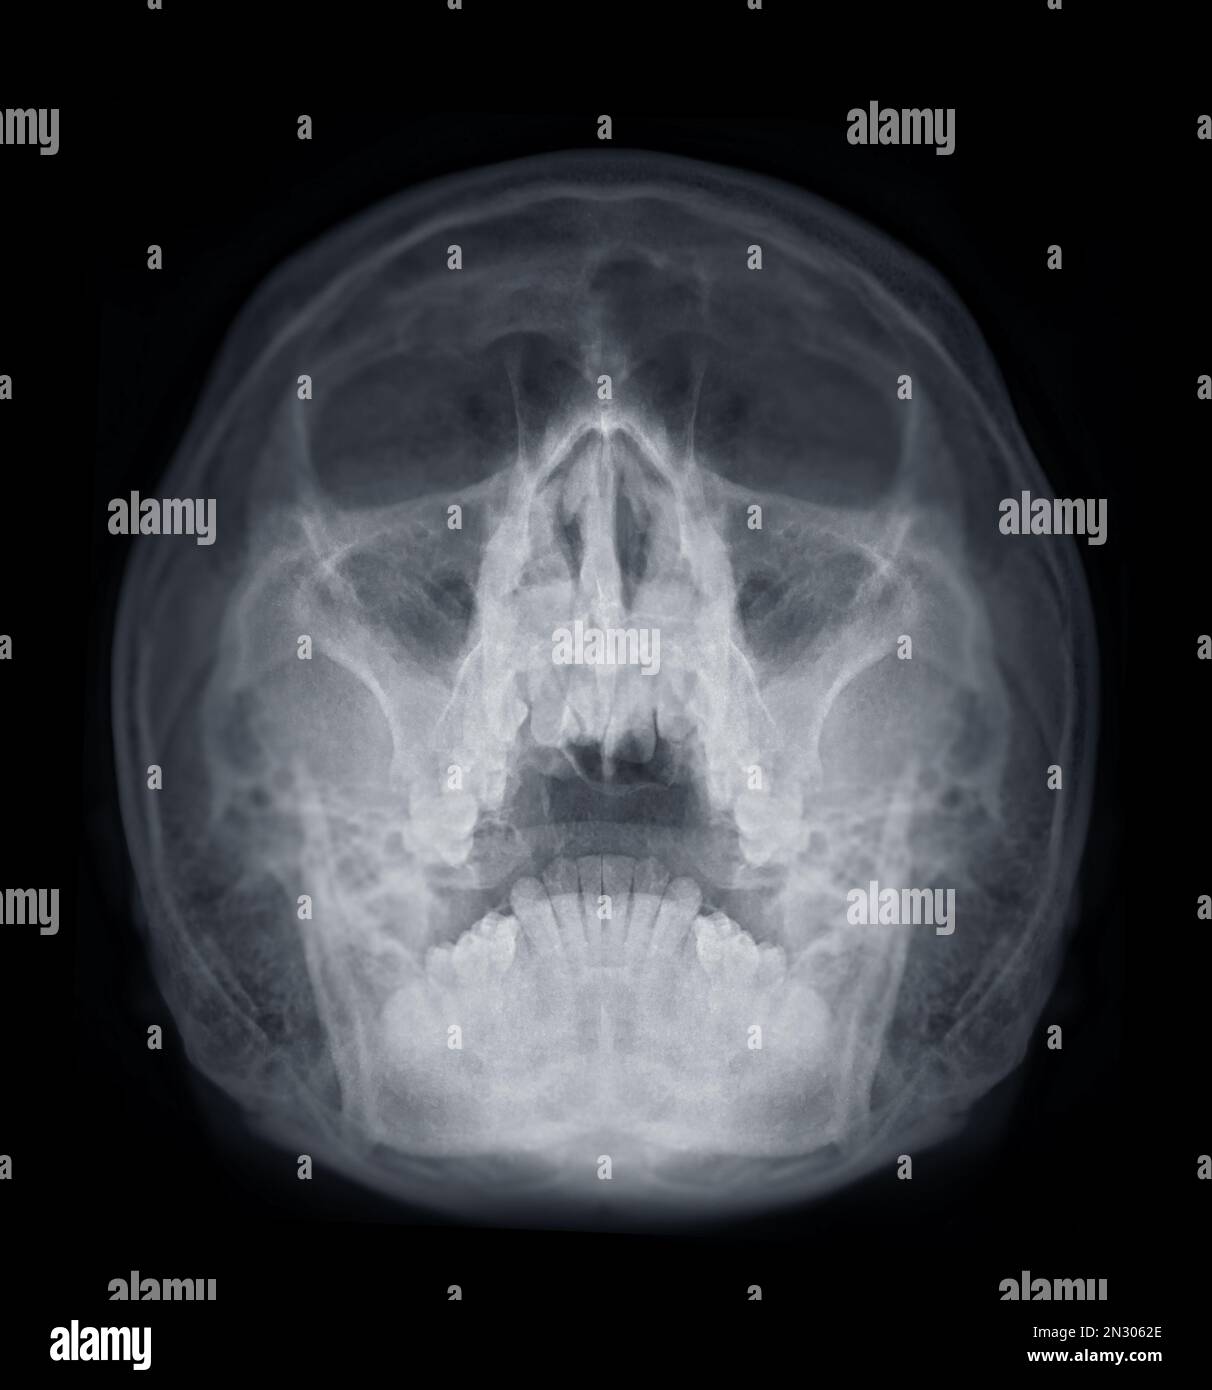

Sinusitis. film xray skull AP ( anterior posterior ) show infection Can An X Ray Show Sinus Infection When the sinus openings become blocked or too much mucus builds up, bacteria and other germs can grow. This can lead to an infection and. Perform an anterior rhinoscopy (using an otoscope or a nasal speculum and headlight) to identify: It's common and usually clears up on. You may also need a. Inflammation and fluid in the sinuses (sinusitis) infection.. Can An X Ray Show Sinus Infection.